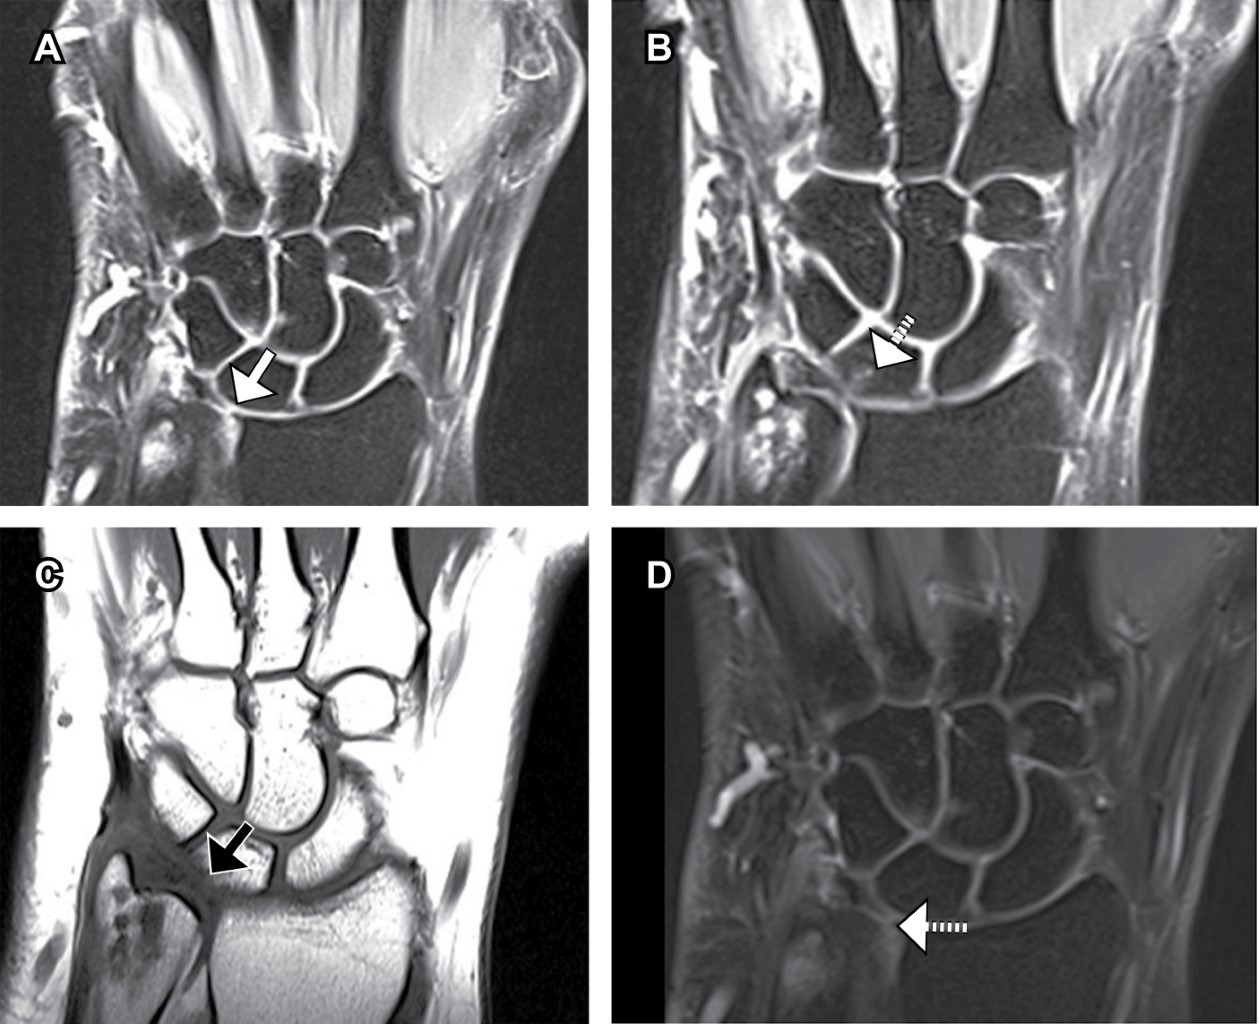

Luego de estudios radiológicos, se observa una varianza cubital neutral, la epífisis distal y apófisis estiloides cubital presentan cambios quísticos erosivos subcondrales con edema medular reactivo de distribución difusa, sin fracturas o fisuras, siguiendo el eje de la superficie articular. Imagen similar, pero en menor grado en el borde proximal dorsal del semilunar, leve edema difuso del fibrocartílago triangular, sin desgarro ni desinserción (Figura 1).

Figura 1